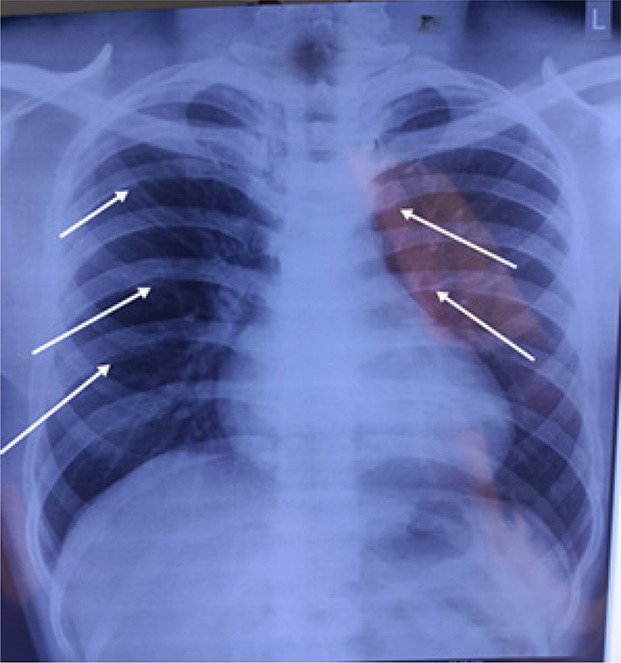

Case presentation: A 20-year-old patient was admitted to our hospital as he complained of headache and palpitations since one week. On examination, the blood pressure in his right upper limb was 180/100 mmHg. The volume of the femoral and the dorsalis pedis pulses was found to be reduced bilaterally. The patient was started on antihypertensive medication labetalol 10 mg injection intravenously immediately. After clinical suspicion and a series of investigations, the patient was diagnosed with severe CoA, distal to the origin of the left subclavian artery via computed tomography (CT) aortogram. The patient was managed by coarctoplasty with stenting.

Discussion: The most striking examination findings indicative of CoA include decreased lower limb pulses and a blood pressure difference of >20 mmHg across both the lower and upper extremities. It is important to evaluate the blood pressure in both upper and lower limbs to diagnose obstructive vascular diseases.